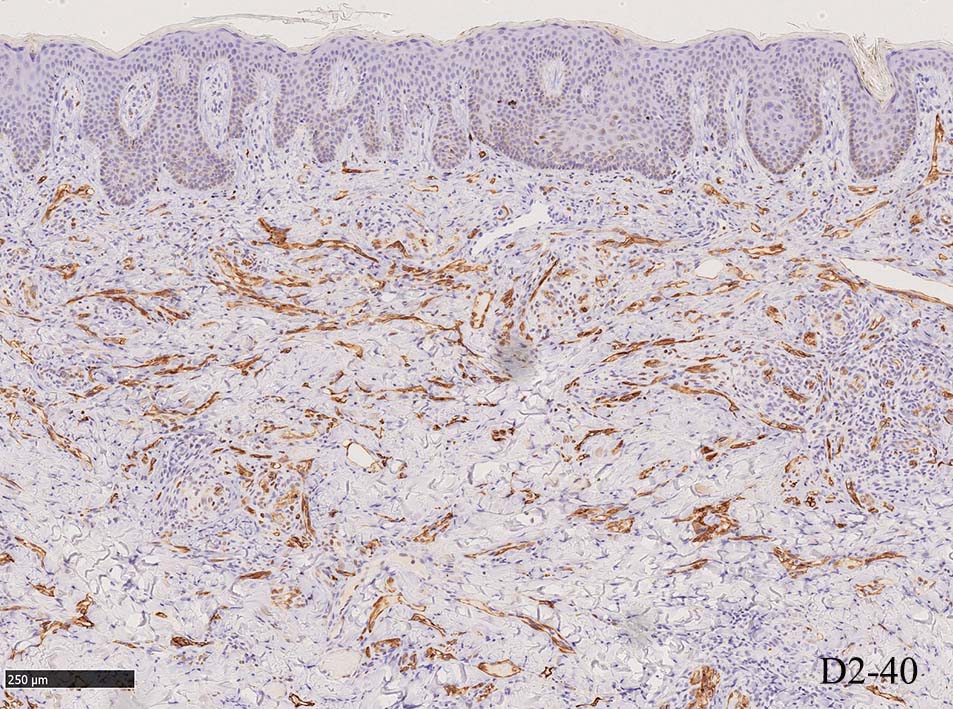

免疫染色, 分子病理学的検査

増生細胞はCD31, CD34, Factor Ⅷ, D2-40などが陽性を示す.

HHV-8の潜伏期関連抗原(HHV-8 Latency-associated nuclear antigen: HHV-8 LANA)が市販されており, 核が点状に染色される陽性所見がKaposi肉腫の確定診断に必須となっている.